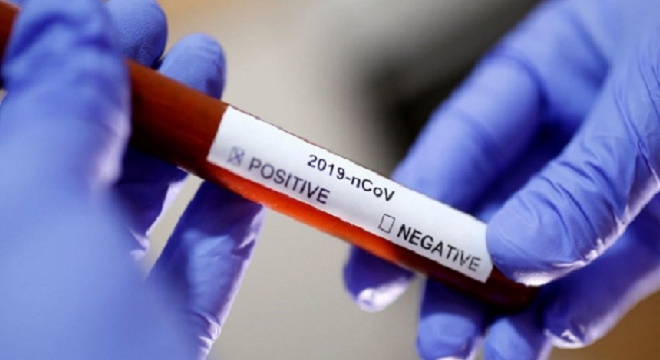

Bilan du Covid-19 en Tunisie (au 25 Juillet) : 18 nouveaux cas portant le total à 1443 Contaminations confirmés (détails)

Tunisie-Tribune (Bilan du Covid-19 en Tunisie) - Le ministère de la Santé a fait savoir dans un communiqué rendu public ce samedi 25 juillet que

Le Kef : Une nouvelle contamination recensée

Tunisie-Tribune (nouvelle contamination) - Un nouveau cas de coronavirus importé a été recensé ce samedi 25 juillet 2020 au gouvernorat

Bilan du Covid-19 en Tunisie (au 24 Juillet) : 19 nouveaux cas importés portant le total à 1425 Contaminations confirmés (détails)

Tunisie-Tribune (Bilan du Covid-19 en Tunisie) - Le ministère de la santé a annoncé que le nombre des cas confirmés de coronavirus est passé

Coronavirus : plus de 4 millions de cas recensés aux Etats-Unis

Tunisie-Tribune (Coronavirus) - Avec plus de 144 000 décès officiellement recensés, les Etats-Unis sont de loin le pays le plus endeuillé

Sousse : six cas de coronavirus enregistrés

Tunisie-Tribune (coronavirus) - Le directeur régional de la Santé à Sousse Mohamed Ghodhbani a indiqué, ce jeudi 23 juillet 2020

Bilan du Covid-19 en Tunisie (au 23 Juillet) : 12 nouveaux cas importés portant le total à 1406 Contaminations confirmés (détails)

Tunisie-Tribune (Bilan du Covid-19 en Tunisie) - Le ministère de la santé a annoncé ce 22 juillet 2020, que 945 tests ont été effectués

Covid-19 : Nouveau classement des pays

Tunisie-Tribune (Nouveau classement des pays) - Le ministère de la Santé a publié, ce jeudi 23 juillet 2020, le nouveau classement des pays

Bilan du Covid-19 en Tunisie (au 22 Juillet) : 5 nouveaux cas importés portant le total à 1394 Contaminations confirmés (détails)

Tunisie-Tribune (Bilan du Covid-19 en Tunisie) - Le ministère de la Santé a annoncé ce mercredi 22 juillet 2020 que les analyses effectuées